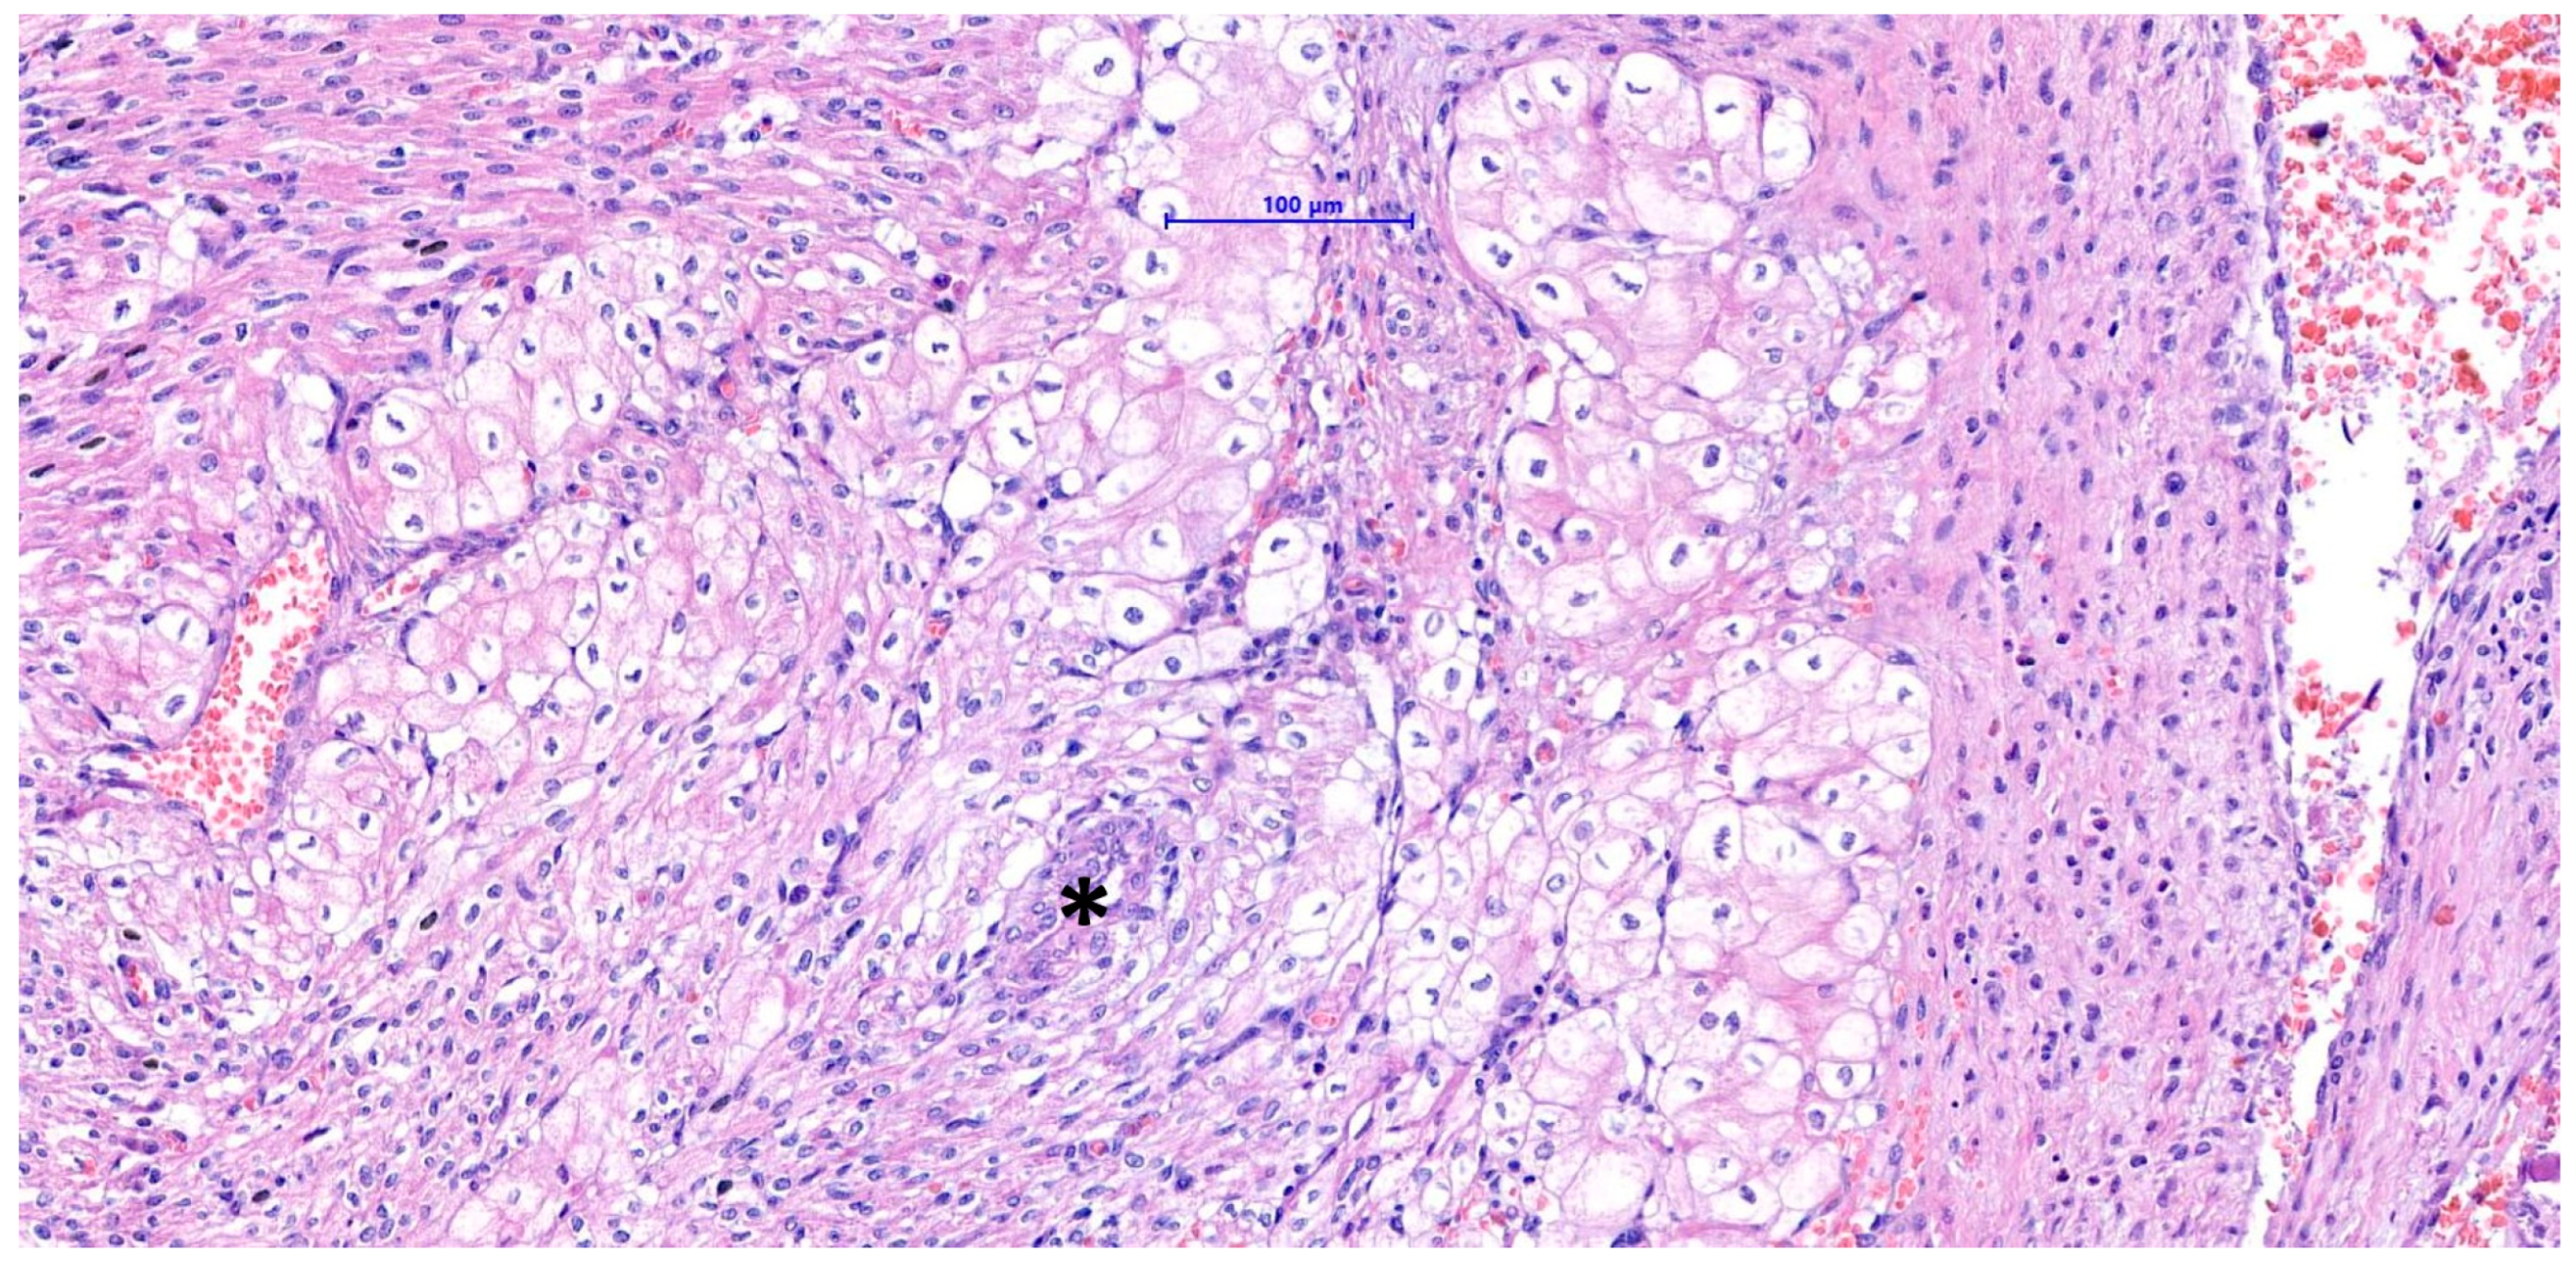

Ultrasound, Histomorphologic, and Immunohistochemical Analysis of a Cardiac Tumor with Increased Purkinje Cells Detected in a Canine Fetus 42 Days into Pregnancy

2.2. Histopathology, Histochemical, and Immunohistochemical Studies